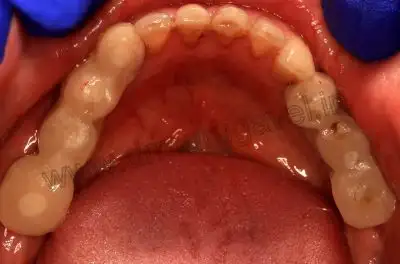

Pre-op upper occlusal view

Post-op upper occlussal view